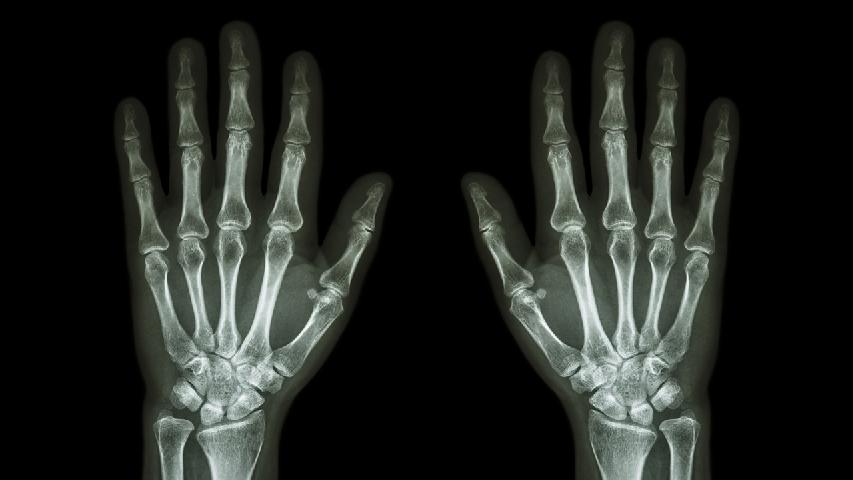

女性類風(fēng)濕關(guān)節(jié)炎初期癥狀主要有晨僵、關(guān)節(jié)腫脹、關(guān)節(jié)疼痛、疲勞乏力。 1、晨僵 早晨起床后關(guān)節(jié)僵硬感持續(xù)超過30分...

風(fēng)濕病可能引發(fā)關(guān)節(jié)畸形、心血管疾病、肺部病變、腎臟損害等并發(fā)癥。風(fēng)濕病屬于自身免疫性疾病,長期炎癥反應(yīng)可導(dǎo)致多系...